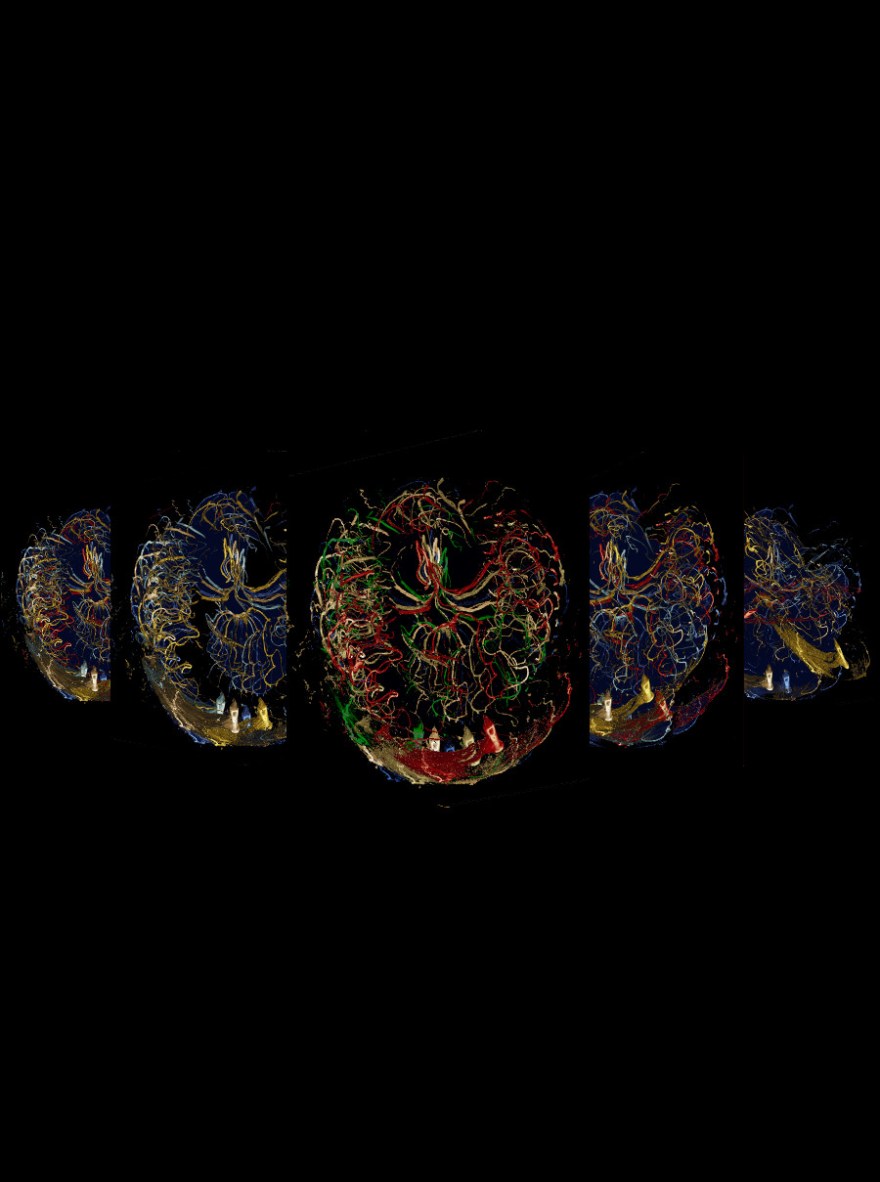

This version of Firefly Trails was my entry into the 2014 ISMRM Art Challenge. It consists of 5 panels of overlapping time of flight MR images.The colours in the middle panel were intended to be reminiscent of the colours in the Italian flag.

Time of Flight (TOF) MRI images are acquired by ‘tagging’ or exciting blood in an artery, ‘below’ the field of view, allowing that tagged blood to travel into the brain, along the arteries, and then acquiring an image before the excited signal has a chance to relax. The result is an amazing snap-shot of the arteries in the brain. When I first saw the TOF images produced by our 7T MRI, it looked like someone had thrown sparking streamers at the screen. The pathways were incredibly crisp, but there were these occasional hyper-intense pixels that seemed to sparkle in the 3 dimensional view of it. I spent a long time trying to develop colormaps that would allow me to convey that 3D feel in the 2 dimensions of a still image. I don’t think I ever quite succeeded, but then I started trying to translate and overlay the images in a way that conveyed the sense of motion I got paging through the data sets.

The results can be seen in this poster. Each panel is composed of overlapping TOF images from the same brain. From left to right the translations and rotations applied to the 2D images become more complicated. Even though I didn’t place in the art challenge, I was pleased with the poster I entered.